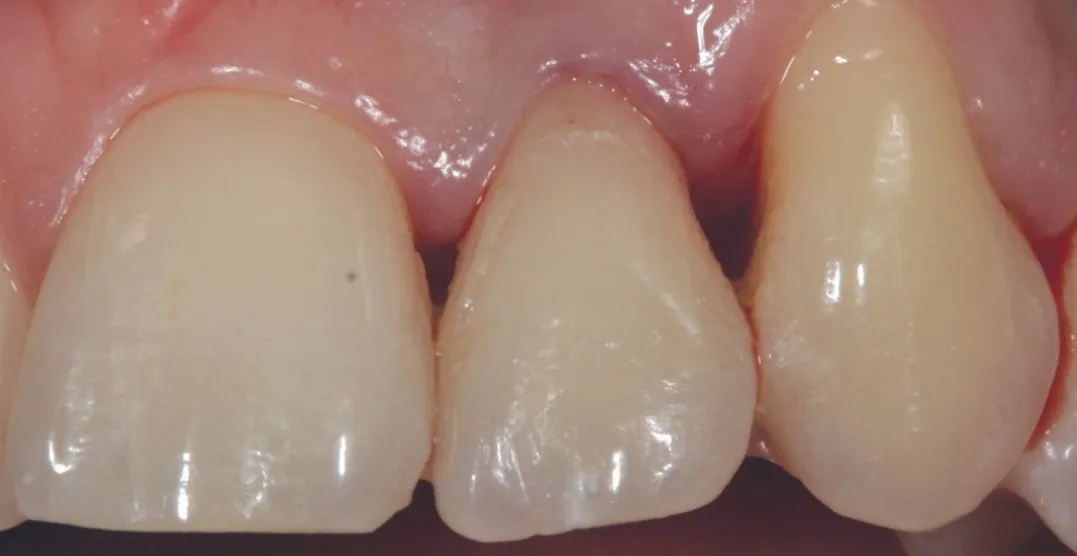

3 号病例 - Patrick EXBRAYAT 医生(图 36 至 49)

女性患者,侧切牙 12 发育不全,长期使用临时修复手段。

图 48 :术后 1 年口内情况。